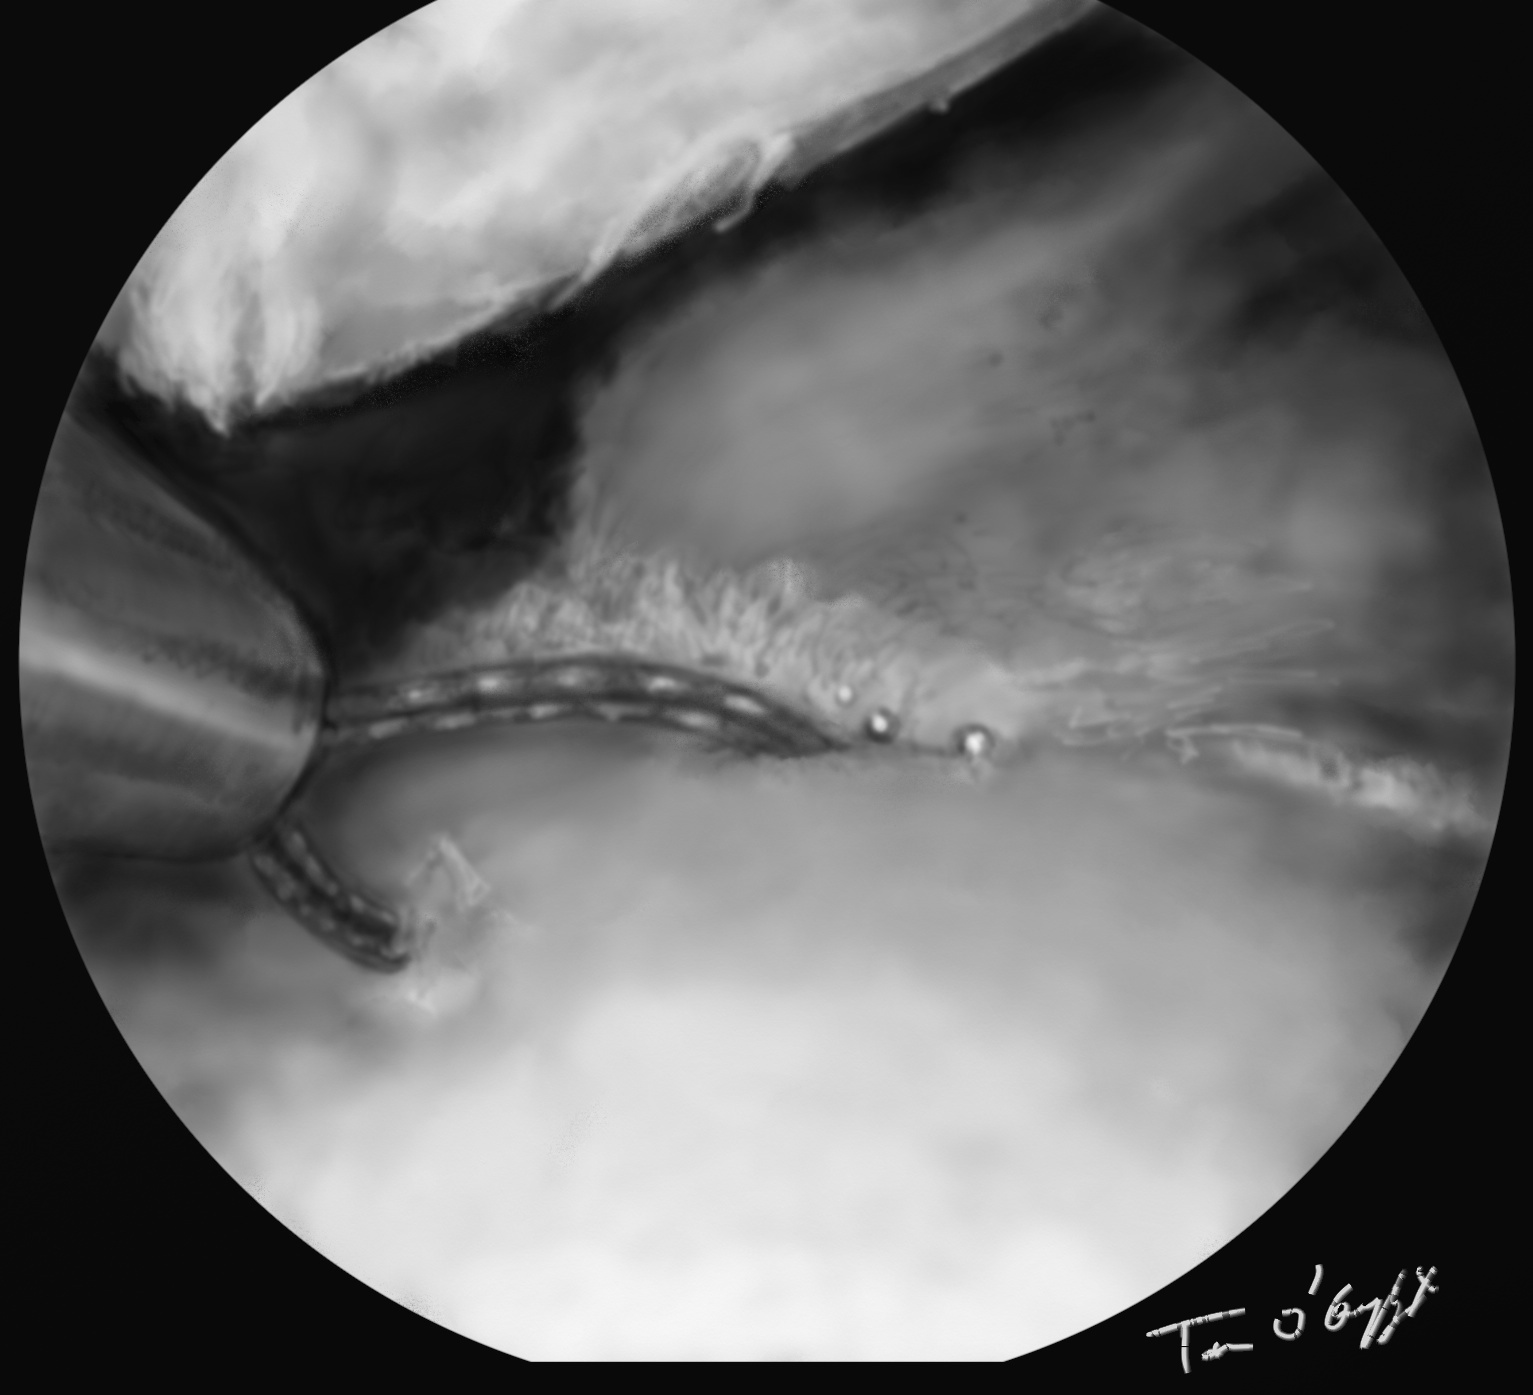

genou arthroscopie menisque ciseau shaver

arthroscopie régularisation au ciseau d’une languette méniscale

L’arthroscopie visualise alors exactement la déchirure méniscale, permet de réduire une luxation en anse de seau, de découper et régulariser une déchirure en languette, de suturer une fissure longitudinale ou en cas de désinsertion périphérique. En sachant que les atteintes externes ont une bonne chance de cicatrisation donc suture, et internes quasiment aucune donc exérèse.